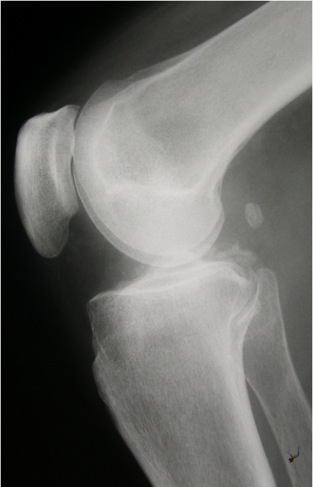

RIGHT KNEE:

Frontal and lateral views are submitted.  All osseous structures are in normal anatomic position.

Bone density is adequate.  Small osteophytes are noted at the distal femur and proximal tibia.  The medial tibiofemoral joint space is mildly reduced.  Calcification is noted within the tibiofemoral joint space, parallel to the subchondral bone.  There is a well-defined ossification in the soft tissues, posterior to the femoral condyles.

IMPRESSIONS:

1.	Calcium pyrophosphate deposition disease.

2.	Mild degenerative joint disease.

3.	Fabella.